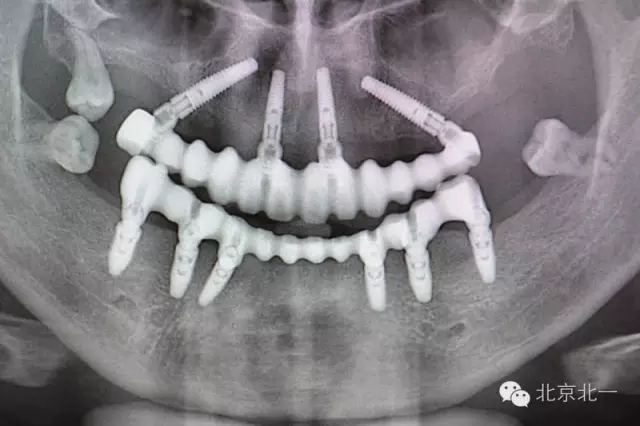

圖五:術(shù)后全景片

上頜傾斜植入,即刻修復(fù),永久固定修復(fù)病例